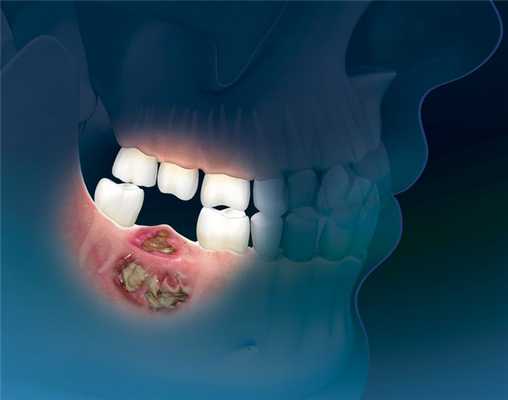

(Слева) На изображении показан ПКР альвеолярного гребня нижней челюсти с распространением на тело нижней челюсти (Т4а). Обратите внимание на инвазию нижнего альвеолярного нерва - момент, важный для полной резекции опухоли.

(Справа) При аксиальной КУ с КУ визуализируется объемное образование неоднородной структуры, разрушающее тело нижней челюсти слева. Опухоль распространяется кнаружи между десной и щекой, прорастая в щеку, а также кнутри, прорастая в дно полости рта. Опухоль (T4aN1) была полностью удалена, дефект тканей закрыт комбинированным лоскутом. (Слева) На фото у мужчины 66 лет виден патологический очаг В неправильной формы с уплотнением и изъязвлением тканей в области альвеолярного гребня верхней челюсти, начинающийся на уровне первого премоляра. Была выполнена биопсия, подтвердился инвазивный плоскоклеточный рак. Клинически стадия была определена как T2N0.

(Справа) При МРТ Т1ВИ в аксиальной проекции у этого же пациента определяется мягкотканный компонент снаружи от альвеол нижней челюсти; жировая ткань (по сравнению с противоположной стороной) отсутствует. На томограммах не определяется убедительных признаков инфильтрации костного мозга, что позволяет выполнить частичную максиллэктомию.